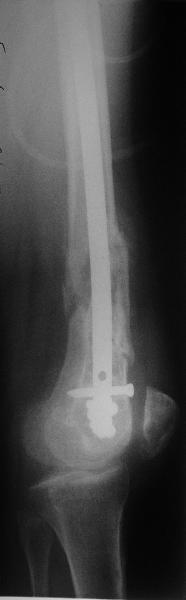

По прямой проекции неплохо. Что за стержень?

Антеградный остеосинтез при дистальных переломах бедра мы применяем давно, этот материал обобщен в канд. диссертации Александра Виноградского.

Предприятие ЦИТО выпускает доработанные нами гвозди, которые хорошо годятся для дистальных переломов, да и недороги. Можно вводть в дистальное овальное отверстие 3 винта, которые заклинивают друг друга.

Большеберцовые стержни отлично выполняют роль ретроградных бедренных. Конечно, которые не 9, а 12 мм в диаметре.

Примеры приложены.

Алекс, как Вы можете говорить, что "по прямой проекции неплохо"!? :( Гвоздь в суставе !!!

Снимаю свои претензии. На втором из снимков, которыми Вы хвастаетесь, гвоздь тоже в суставе, и ничего :(

И какие страшные проблемы от этого тянут аж на три восклицательных знака?

Если даже будет patellar impingement, это решается удалением после сращения.